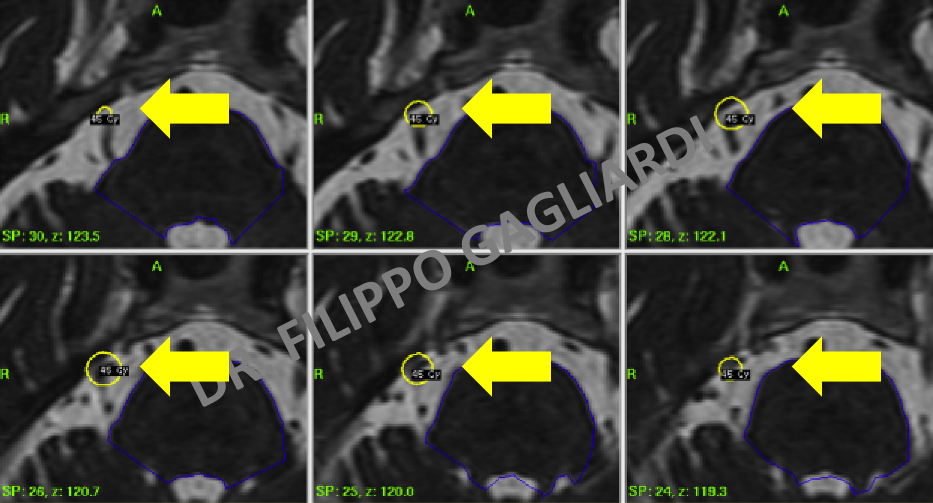

Nell'immagine successiva il piano di trattamento di una nevralgia trigeminale trattata con radiochirurgia. Il fascio di radiazioni si concentra su un punto specifico del nervo (cerchio giallo) per distruggere selettivamente le fibre che portano le informazioni del dolore.